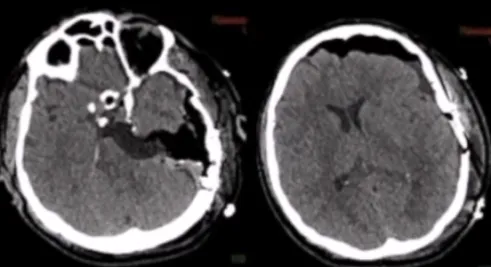

Labbé静脉呈现出规则的解剖形态,术前CT扫描有助于评估骨骼解剖,包括肿瘤的钙化、岩尖的气化以及乙状窦后空间。同样重要的是评估中颅窝底在膝状神经节上方可能存在的裂开,以及在颈动脉管水平可能存在的裂开,以减少在手术入路过程中对这些结构的损伤风险。此外,福教授还评估了颈静脉球的高度与内听道的关系。

术前血管造影可以评估肿瘤的血供。这个序列显示了来自咽升动脉的血供,以及来自颈内动脉的硬脑膜支,由下外侧干和脑膜垂体干表示。通过在咽升动脉处放置线圈进行栓塞,手术前一天进行,可以显著减少术中出血。

术后CT未显示任何术后并发症,术后MRI显示脑膜瘤几乎完全切除。